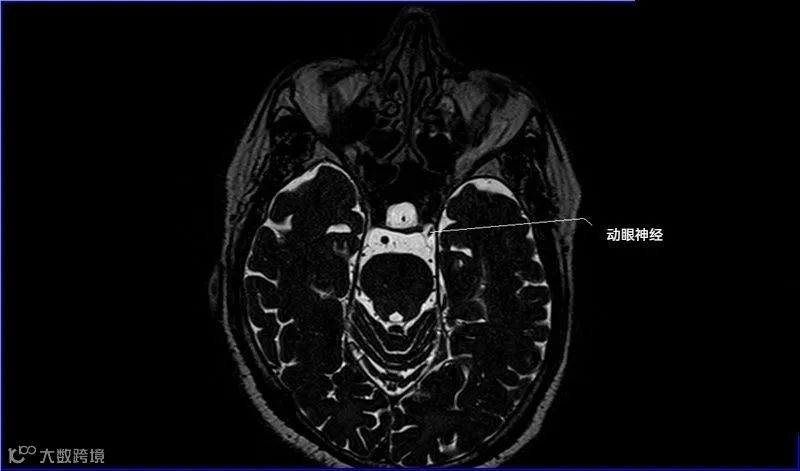

一嗅二视三动眼,四滑五叉六外展,

七面八听九舌咽,迷走及副舌下全。